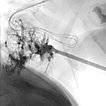

Aufgrund des schnellen Größenwachstums und der rezidivierenden, schmerzhaften Thrombophlebitiden wurde eine Sklerosierungstherapie durchgeführt. Die hier dargestellte Kontrastmittelinjektion über eine eingebrachte Punktionsnadel zeigt eine weitgehende Kontrastierung der venösen Malformation, somit gute Voraussetzungen für eine erfolgreiche Sklerosierungstherapie.

In der digitalen Subtraktionsangiographie nach KM-Injektion über die gleiche Nadel zeigt sich ebenfalls sehr gut die fast vollständige Füllung der venösen Malformation aus dieser Nadelposition. Nur kleine, sehr dünnlumige Kommunikationsvenen stellen sich dar. Daher kann aus dieser Nadelposition ein Großteil der VM sklerosiert werden.